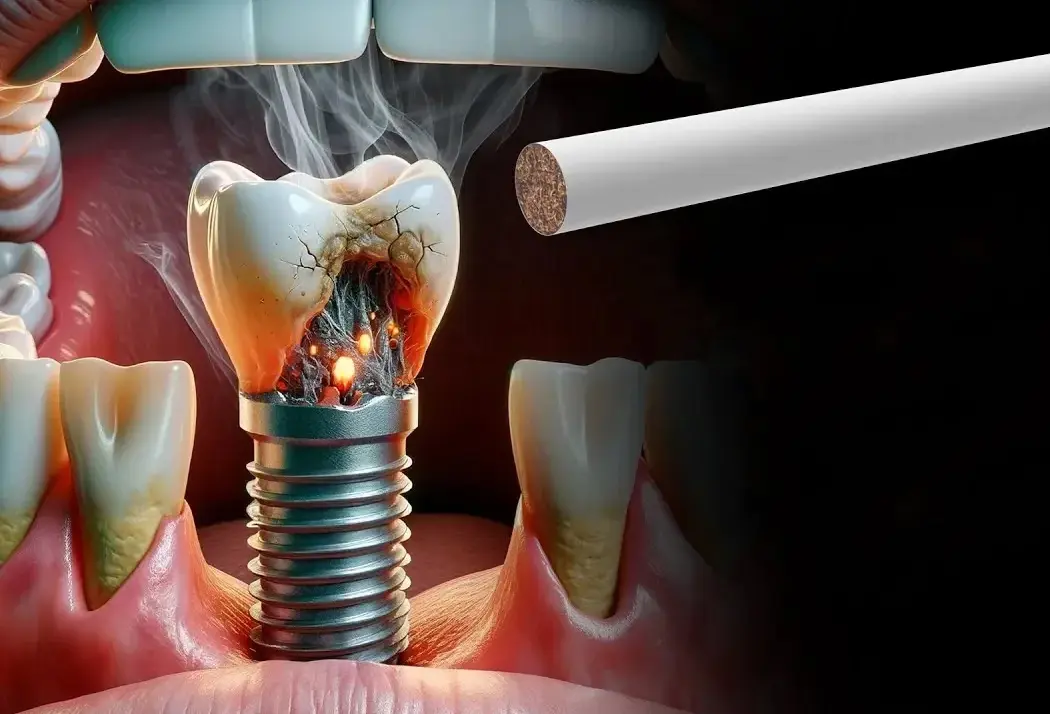

سوال: چه تغییراتی در سبک زندگی ممکن است قبل از کاشت ایمپلنت دندان توصیه شود؟

پاسخ: دندانپزشکان اغلب توصیه می کنند که بیمار سیگار نکشد، بهداشت دهان و دندان را رعایت کند و احتمالاً رژیم غذایی و عادات خود را برای بهبود سلامت کلی و افزایش موفقیت ایمپلنت تنظیم کند.